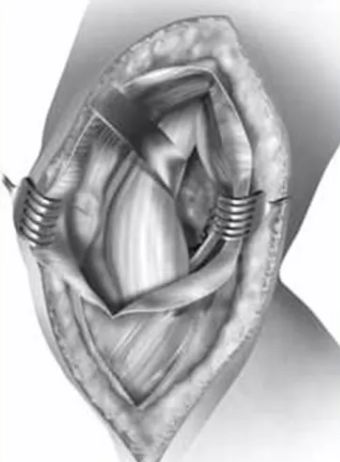

swashbuckler入路

在胫骨结节外侧沿髌骨外侧缘行皮肤切口,延伸至髌骨的外上角,切口长度约12-15cm。

锐性分离膝关节部位皮瓣直至暴露外侧髌韧带,沿髌韧带作梯形手术切口,暴露膝关节,如图1,该切口远端起始于髌腱胫骨止点外侧,沿髌骨边缘的髌韧带延伸至股外侧肌肌腹。

后按一下四个步骤进行股骨远端暴露:1. 使用手指将髌腱从髌后脂肪垫上钝性分离;2. 完全切除髌后脂肪囊和滑囊至半月板韧带水平,注意此时需保护半月板和半月板间韧带;3. 完全松解髌韧带远方胫骨结节止点;4. 最后松解髌韧带上方以获得进入髌上囊的空间。

在胫骨近端靠近内侧半月板水平放置霍夫曼拉钩以牵开髌骨,在髌上囊水平放置另一个霍夫曼拉钩牵开近段股中间肌完成微创swashbuckler入路。

沿髌韧带所作的梯形手术切口,注意该梯形手术切口仍位于髌韧带内而未延伸至股外侧肌腹

微创swashbuckler入路与股骨轴线呈30度角所拍摄的图片。图中整个股骨远端关节面得到接近完整的暴露